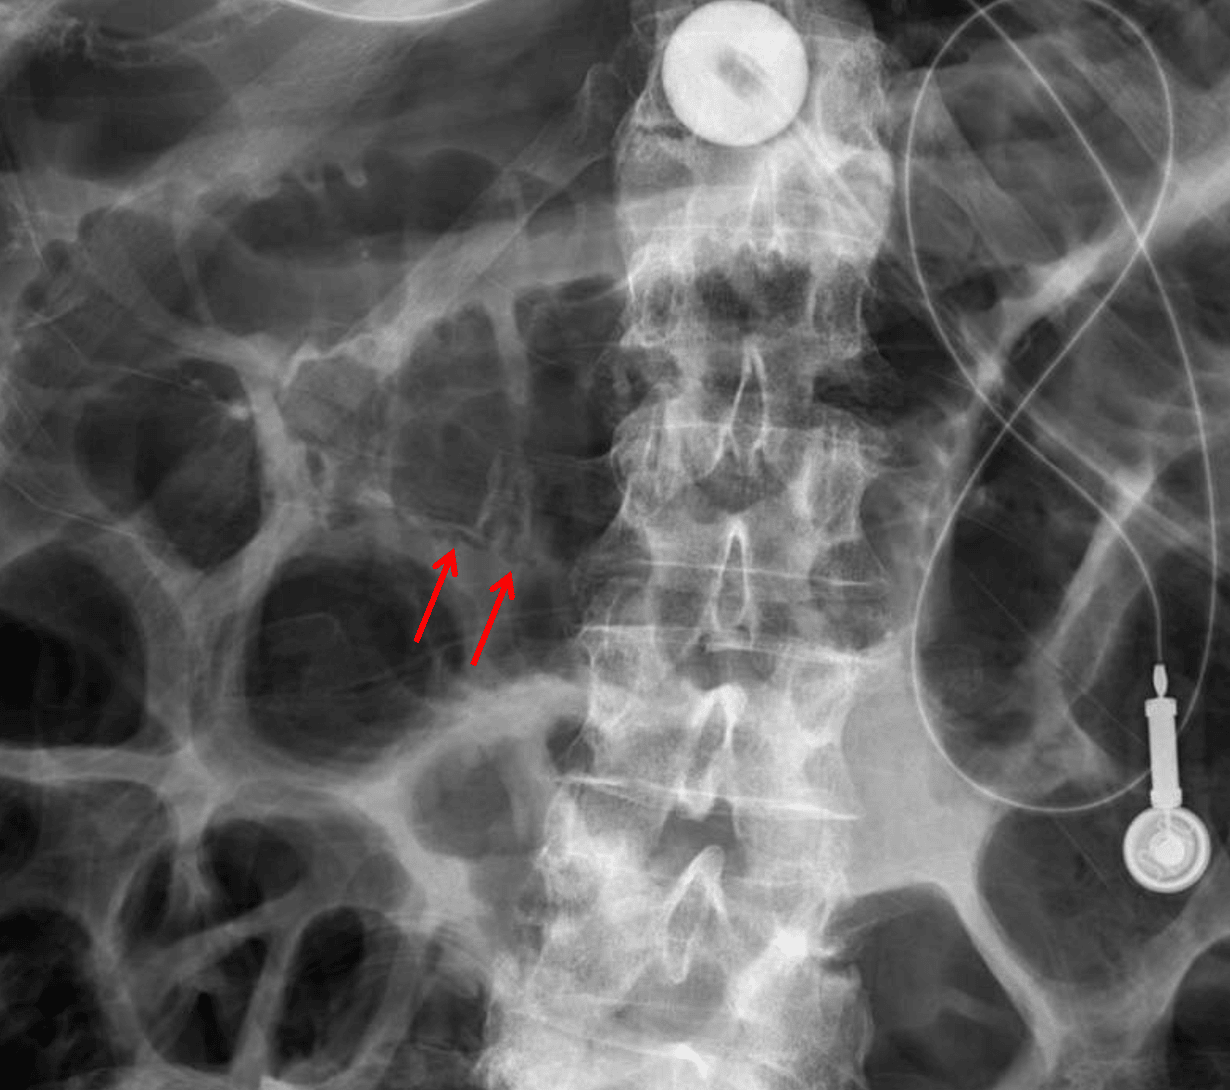

- Linear lucency along the inferior wall of the proximal transverse colon

Linear lucency along the inferior wall of the proximal transverse colon is concerning for pneumatosis. Recommend CT for further evaluation.

Linear lucency along the inferior wall of the proximal transverse colon concerning for pneumatosis (red arrows).